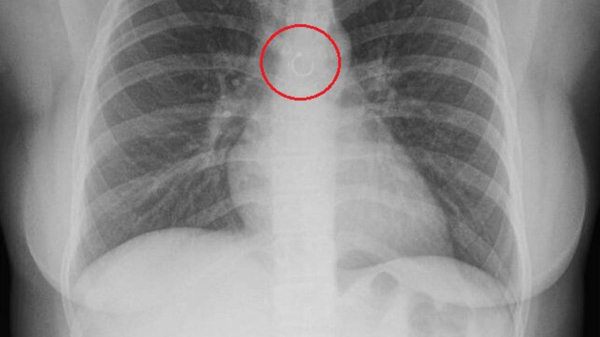

Woman discovers missing nose ring traveled to her lungs, causing month-long cough

A TikToker in Mexico thought her cough that wouldn’t go away was just a reaction to the changing weather. Instead, it was her own nose ring, lodged deep within her lungs.

In s, she shared that the stray accessory sat a mere 0.5 millimeters from her aorta, Jam Press reported.

Deyanira, who has a large number of piercings, didn’t initially notice the jewelry was missing. It wasn’t until she developed a “chronic cough” lasting over a month that she went to see a doctor.

“The only theory I have, which I told the pulmonologist, is that I fell asleep, the little ball fell out, and that was it,” Deyanira told creatorzine.com.